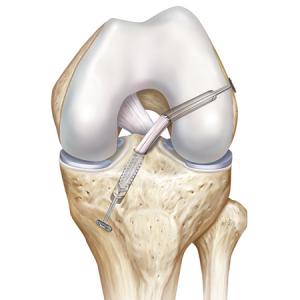

Operative Therapie: Rekonstruktion des vorderen Kreuzbandes

Kreuzbandrekonstruktion führen wir ausschliesslich in kameraassistierter Technik, der sogenannten Arthroskopie, durch. Bessere Ergebnisse bei kürzeren Operations- und Nachbehandlungszeiten sowie entsprechend weniger Schmerzen und ein besseres kosmetisches Ergebnis werden hiermit erreicht. Somit kann eine frühzeitige Sport- und Arbeitsfähigkeit als bei älteren Methoden erreicht werden. Es benötigt jedoch ein Höchstmaß an Erfahrung, damit diese hochspezialisierten Techniken den erwünschten Erfolg erzielen. Von uns können sowohl eine Einzel- als auch Doppelbündeltechnik, bei der beide anatomisch wirksamen Bündel rekonstruiert werden, durchgeführt werden. Beide Techniken führen wir durch, weil bekannt ist, dass das antero-mediale Bündel in höheren Beugegraden Stabilität gibt, während das postero-laterale Bündel hauptsächlich strecknah stabilisiert. Diese beiden Bündel sind jedoch jederzeit als funktionelle Einheit zu sehen. Um also die ursprüngliche Biomechanik im Knie wieder herzustellen bedarf es einer der ursprünglichen Anatomie identischen Rekonstruktion. Deshalb wird individuell eine instabilitätsabhängige Operationstechnik angewendet.

Der Ersatz erfolgt in den meisten Fällen mittels einer köpereigenen oder in Fällen von Mehrfachverletzungen mittels einer Spendersehne.

Wir verwenden Sehnen aus der inneren Oberschenkelregion, da sie aufgrund Ihrer Struktur in Länge und Durchmesser den anatomischen Gegebenheiten des Kniegelenkes perfekt angepasst werden können, teilweise sogar nachwachsen und ein kosmetisch sehr gutes Ergebnis zulassen. Zudem zeigen sich im Gegensatz zur Kniescheibensehne (Patellasehne) weniger Schmerzen. Eine weitere Option stellt die Quadrizepssehne oder der Teil einer Sehne aus dem äusseren Unterschenkel dar. Bei Mehrfachverletzungen des Kniegelenkes, wenn die Entnahme der Sehnen die Instabilität nur verlagern würde, können Spendersehnen benötigt werden. Die Fixierung der Sehne im Knochen erfolgt von uns mittels einer doppelten Befestigung, der sogenannten Hybrid-Fixierung. Dieses bedeutet eine deutlich höhere primäre Stabilität als eine einzelne Befestigungsmethode.